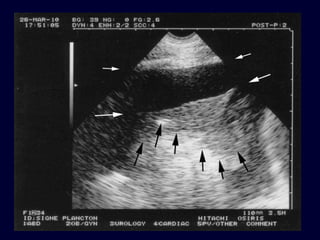

• 81.

Tissue pattern representativeof Alveolar Consolidation Presence of hyperechoic punctiform images Presence of hyperechoic punctiform imagesrepresentative of air bronchogramsrepresentative of air bronchograms Pleural effusion Lower lobe